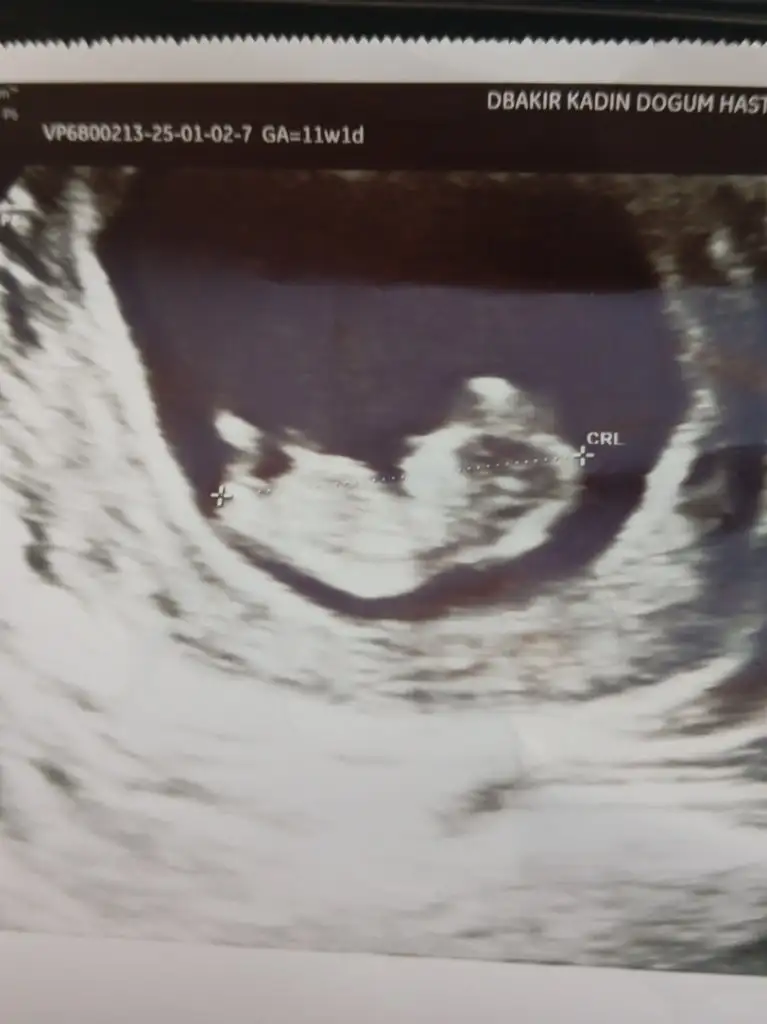

Bana da erkek gibi geldi. Birde bilimselliği yok tabiki ama kalp atışı hızı falan diyolar sizinkisi kaç acaba cinsiyeti öğrenince de söylerseniz tutup tutmadığını gerçekten merak ediyorumKızlar selam 13.haftamdayım kesin bir tahmini olan yada anlayan varsa ultrasın fotoğrafı ekleyeceğim sizce cinsiyeti nedir Eki Görüntüle 3539040

12+5 haftalık sizce cinsiyet nedirBana da erkek gibi geldi. Birde bilimselliği yok tabiki ama kalp atışı hızı falan diyolar sizinkisi kaç acaba cinsiyeti öğrenince de söylerseniz tutup tutmadığını gerçekten merak ediyorum

Erkek bence kesin hem de benim düşüncem buKızlar selam 13.haftamdayım kesin bir tahmini olan yada anlayan varsa ultrasın fotoğrafı ekleyeceğim sizce cinsiyeti nedir Eki Görüntüle 3539040